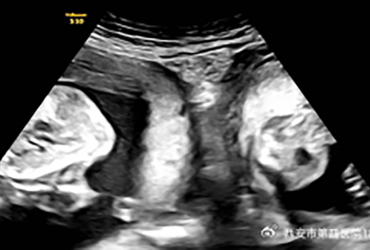

A woman with the rare condition of two uteruses delivered twins, ...